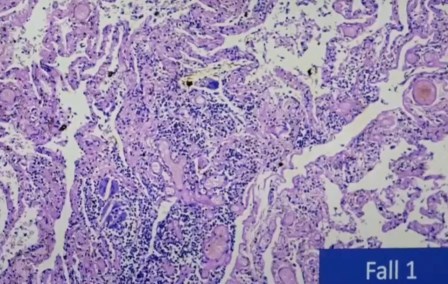

Brónculo-folículo, esto suele verse en enfermedades autoinmunes crónicas, pero no debería ser en pacientes con pulmones normales.

Folículo de linfoma con dos focos que tienen mucha fuerza. Se ven focos de infección que se ven en los de la memoria y los que causan la respuesta del sistema inmunitario